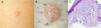

A 62-year-old man presented with a lesion of 2 years’ duration on his right thigh. Physical examination showed a firm nodule with a shiny surface (Fig. 1A). Dermoscopy showed a translucent pink-whitish lesion with scalloped edges and a small central crust, together with fine superficial vessels and white homogeneous spots (Fig. 1B).

Histopathology of the surgically excised lesion showed a markedly hypocellular myxoid mesenchymal proliferation containing stellate cells without atypia and numerous vascular structures (Fig. 1C). These findings were compatible with superficial angiomyxoma.